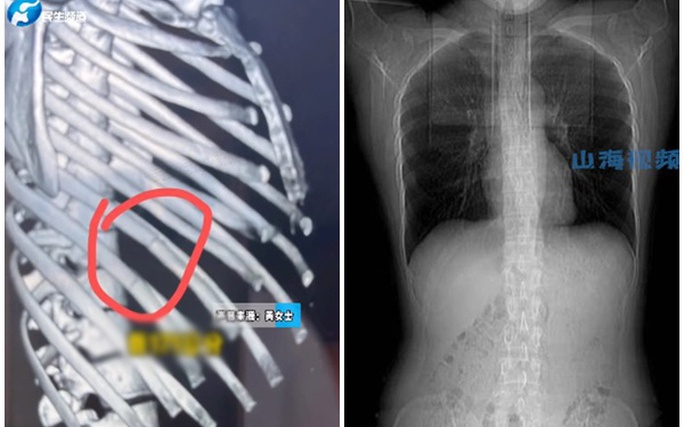

Một cô gái ở Trung Quốc, danh tính chỉ được tiết lộ là họ Huang, đã gãy 4 xương sườn vì ho dữ dội trong lúc ăn đồ cay, báo South China Morning Post (SCMP) đưa tin ngày 5-12.